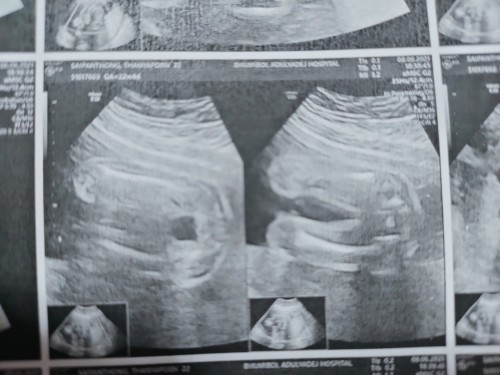

ของเราซาว 20 วีค เปนแบบนี้ค่ะ หมอบอกหมอให้หญิงก่อนน่ะ มีใครดูออกไมค่ะหญิงหรือชายค่ะ

เหมือนผญ.ก็เหมือนนะคะ รอคุณหมอยืนยันอีกทีดีกว่าค่ะ😊

น่าจะผญนะคะไม่มีอะไรโผล่😂😂

หมอบอกว่าไม่มีอะไรโผล่ ได้ ผญ

โผล่มาแบบนี้ค่อย ผช ค่ะ

บ้านนี้ได้ผู้หญิงค่ะ

น่าจะผู้หญิงค่ะ

น่าจะผู้หญิงน่ะ

น่าจะหญิงน่ะค่ะ

น่าจะ ผญ นะคะ